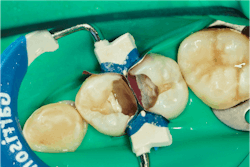

A sectional matrix system is placed with two matrices on, with a single wedge and ring. This is a key part of the procedure. Traditional Tofflemire matrix bands were designed to work with amalgam. While they served dentistry well for decades, as our materials have evolved, so have our needs from a matrix system. Tofflemires are designed to be tightened on the tooth. As the retainer tightens the band, it straightens, leaving us with a flat interproximal wall.

Unfortunately, posterior teeth do not have straight interproximal walls. With amalgam, we could contour the matrix out as we packed our amalgam, but composite is not packable like amalgam, so we don’t have the opportunity to contour the band out and create an anatomic wall. Sectional matrix systems generally come with anatomical matrices that are curved. This is critical to achieving good interproximal contacts with resin composite restorations. In this case, we used Garrison Composi-Tight 3D Fusion system.

A matrix is applied to each tooth and then secured into place with a single wedge. Once this is stable, the interproximal ring is applied to ensure proper separation. This separation force is vital to producing an interproximal contact. If we don’t separate the tooth enough, we will always have an open contact of the width of the matrix itself. The separation uses the PDL of the tooth to create a slight movement of the tooth away from the restoration so when the separation force is removed, the tooth settles back to where it was with a beautiful, cleansable floss-popping contact. While the Garrison ring produces more tooth separation than a traditional Tofflemire matrix, it doesn’t produce enough force to overcome the thickness of two matrices. We will need to phase our next restorative steps in a certain order to account for this.